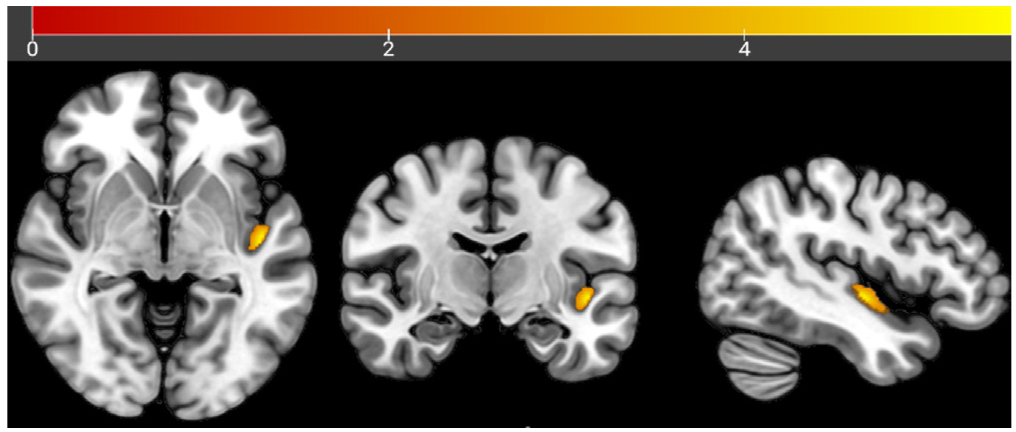

Among the 66 patients, 42 had mild-to-moderate AD, and 24 had severe AD. Among the mild-to-moderate group, 16 had a history of alcohol consumption and 26 did not. Among patients with mild to moderate AD, the proportion of males with a history of alcohol consumption and the proportion of those with a history of smoking were higher than those without such histories (P<0.05) . Among the 24 patients with severe AD, 9 had a history of alcohol consumption and 15 did not. Among the patients with severe AD, the proportion of males with a history of alcohol consumption and the proportion of those with a history of smoking were higher than those without a history of alcohol consumption (P<0.05) . In patients with mild to moderate AD, the GMV of the right angular gyrus in those without a history of alcohol consumption was lower than that in those with a history of alcohol consumption (t=-3.698, P<0.05) . In patients with severe AD who had a history of alcohol consumption, the GMV of the left superior temporal gyrus was lower than that of those without a history of alcohol consumption (t=5.774, P<0.05) .

A history of alcohol consumption appears to significantly influence patterns of gray matter atrophy in AD patients. In mild-to-moderate AD, drinking may be associated with attenuated atrophy in the right angular gyrus, whereas in severe AD, it is linked to increased atrophy in the left superior temporal gyrus. These findings suggest a dual role of alcohol consumption in the progression of AD.